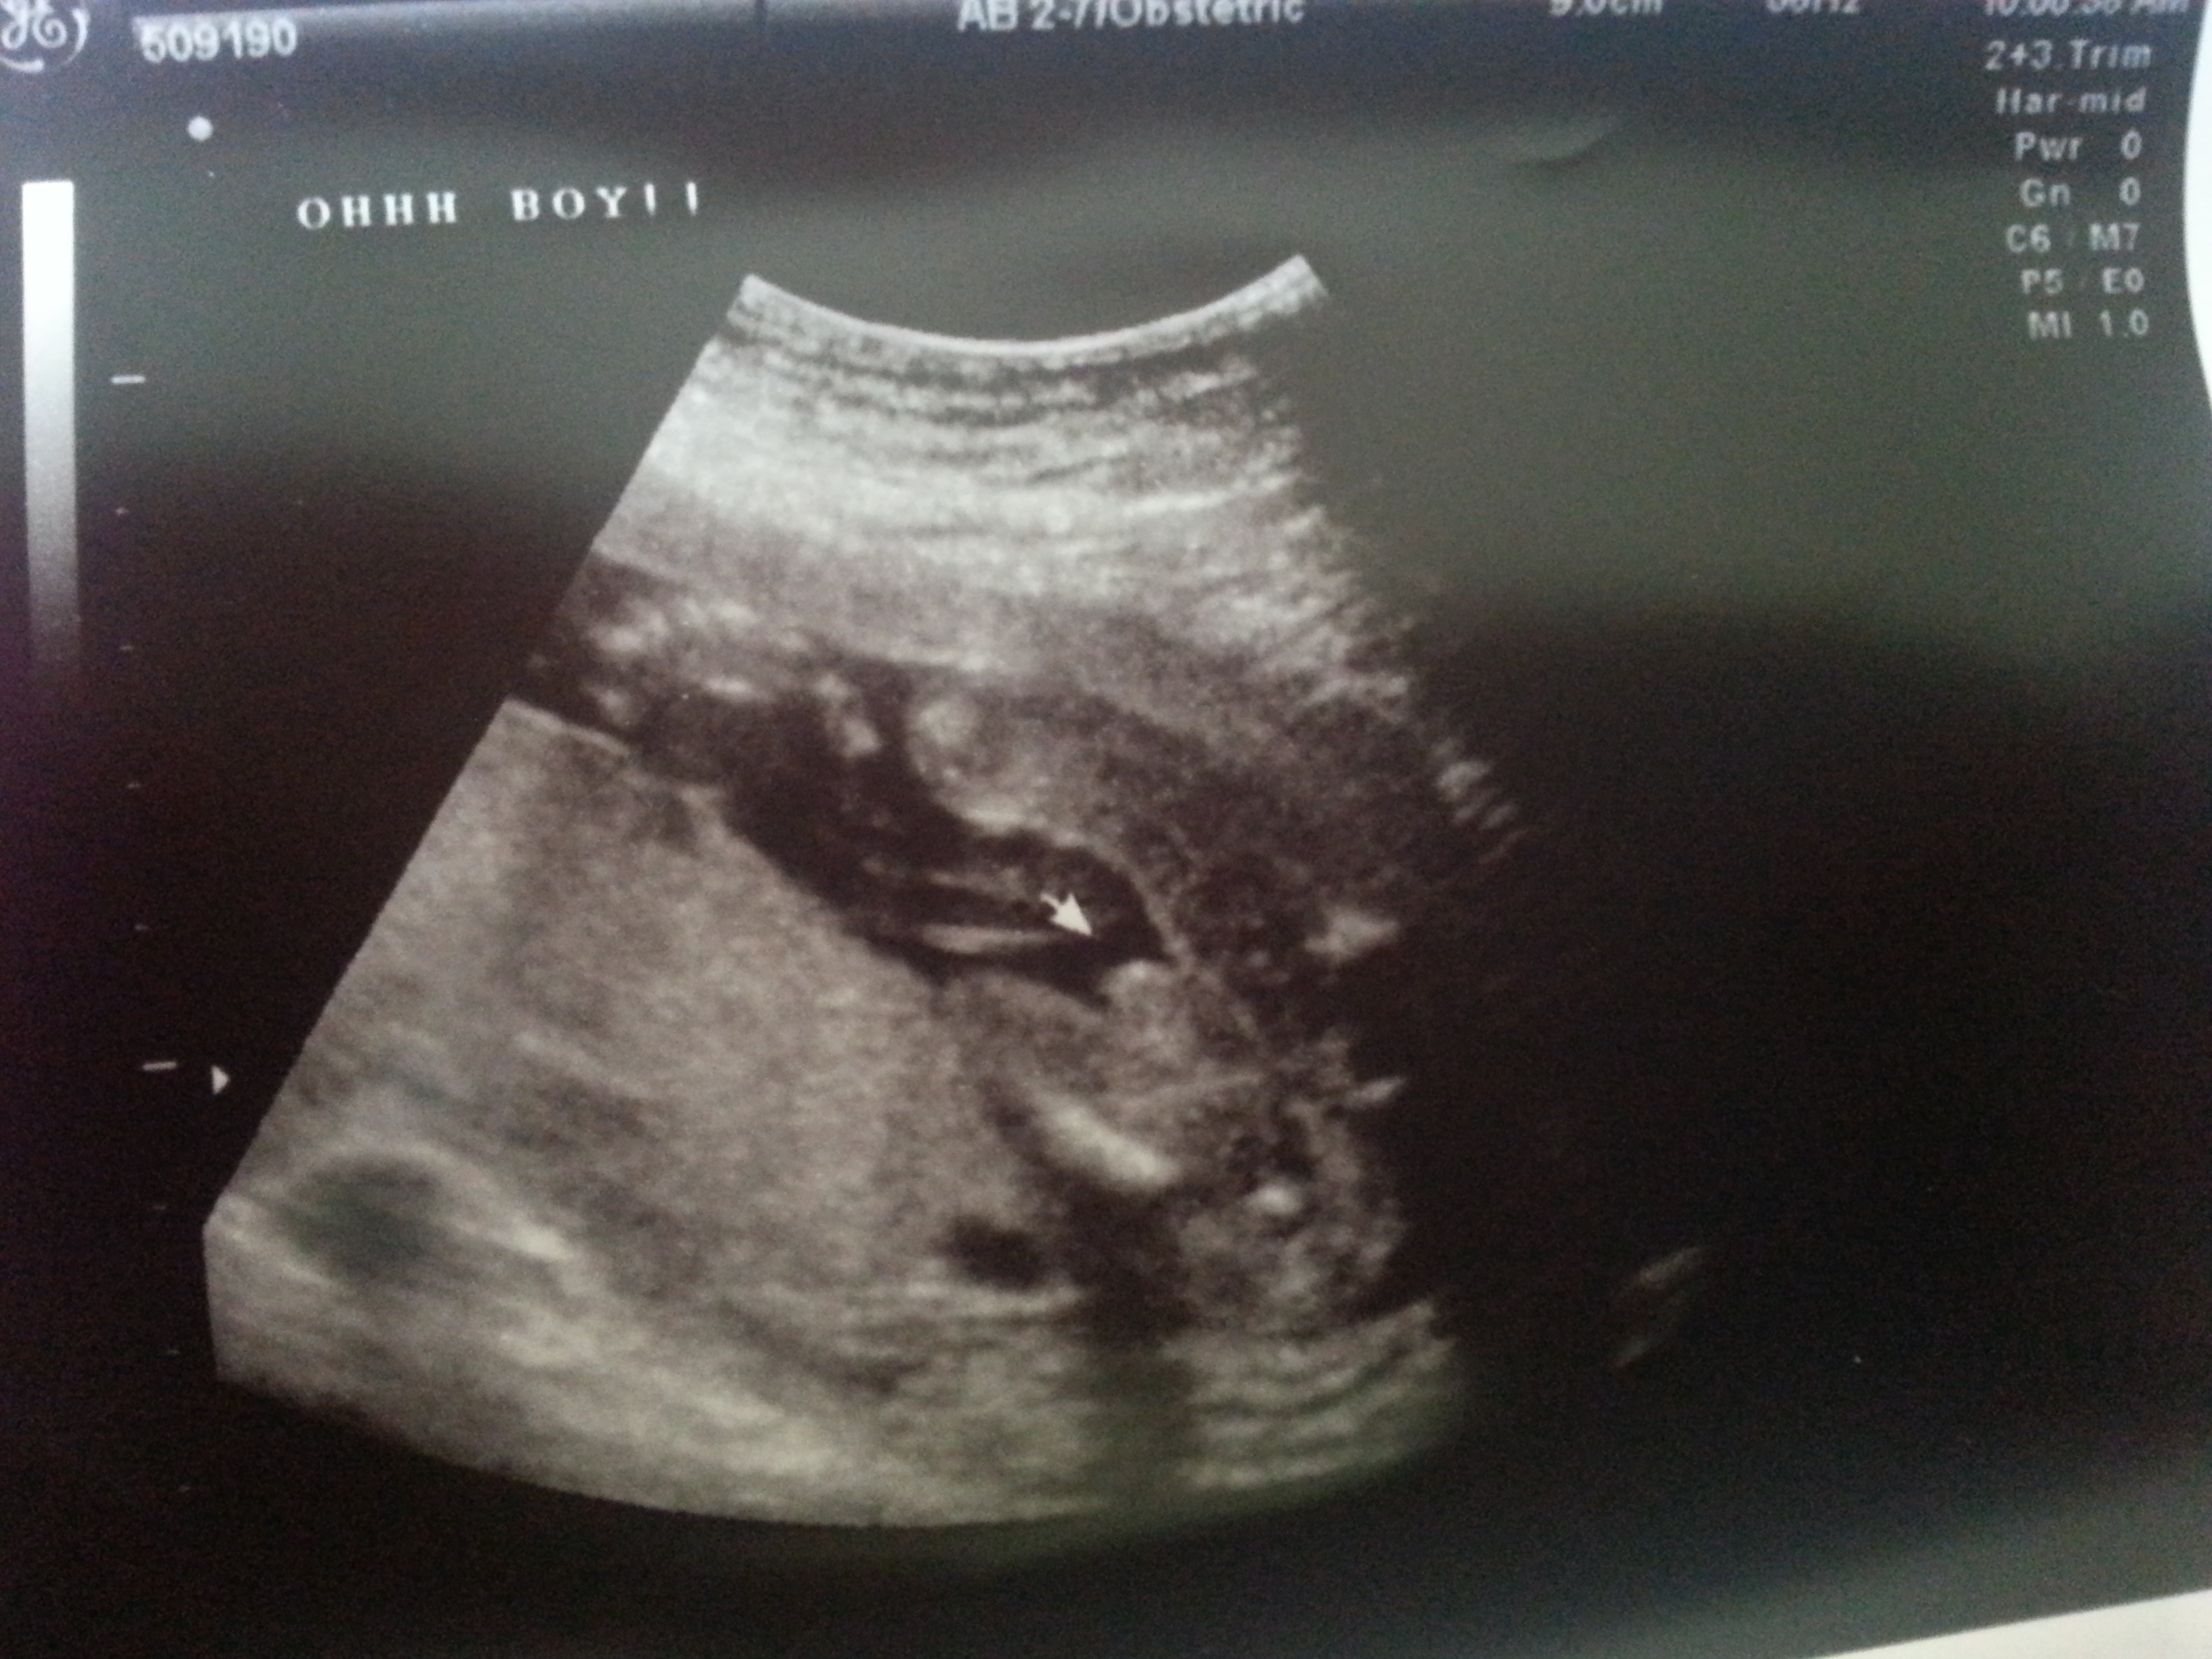

He was very shy and had his legs crossed pretty much the whole time. The tech had to go back a couple of times to check. She even said the cord was in between the legs. I just wanted to double check this is 100% boy. My other two boys were spread egale and they stuff looks a lot bigger than this ones. Attachment 11647